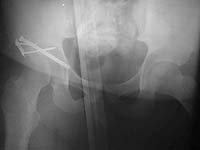

Despite keeping the patient abducted, he dislocated again. Post-reduction xrays again showed a nonconcentric reduction. A CT was done post-op which confirmed no further bone fragments in the joint, no intra-articular hardware and an anatomic reduction of the acetabulum.

Comments on future management will be appreciated. Is his neck shaft angle contributing?

I can't tell if he's reduced on the post-op AP film you included. Do you have any post-op Judet views? It might be easier if we had more films.

Do you have any films of where he is now? Maybe some traction films?

I have never seen an xray of this patient concentrically reduced. He is currently dislocated and cannot be reduced closed.